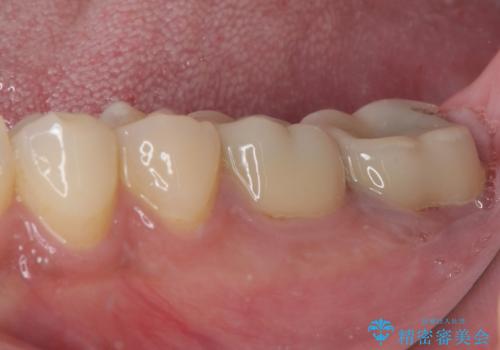

- 間もなく海外赴任という状況で奥歯のクラウンが割れてしまったとのことで来院された患者様です。

下顎の1番奥の歯であり、歯肉に覆われている部分が大きいためセラミックの十分な厚みが取れない状態でした。

強化セラミックを用いたオールセラミッククラウンにて補綴治療を行うこととしました。

十分な土台の高さを確保できない状態であったので、維持力のある土台の形態に整えることで、極力長持ちする治療を心がけました。